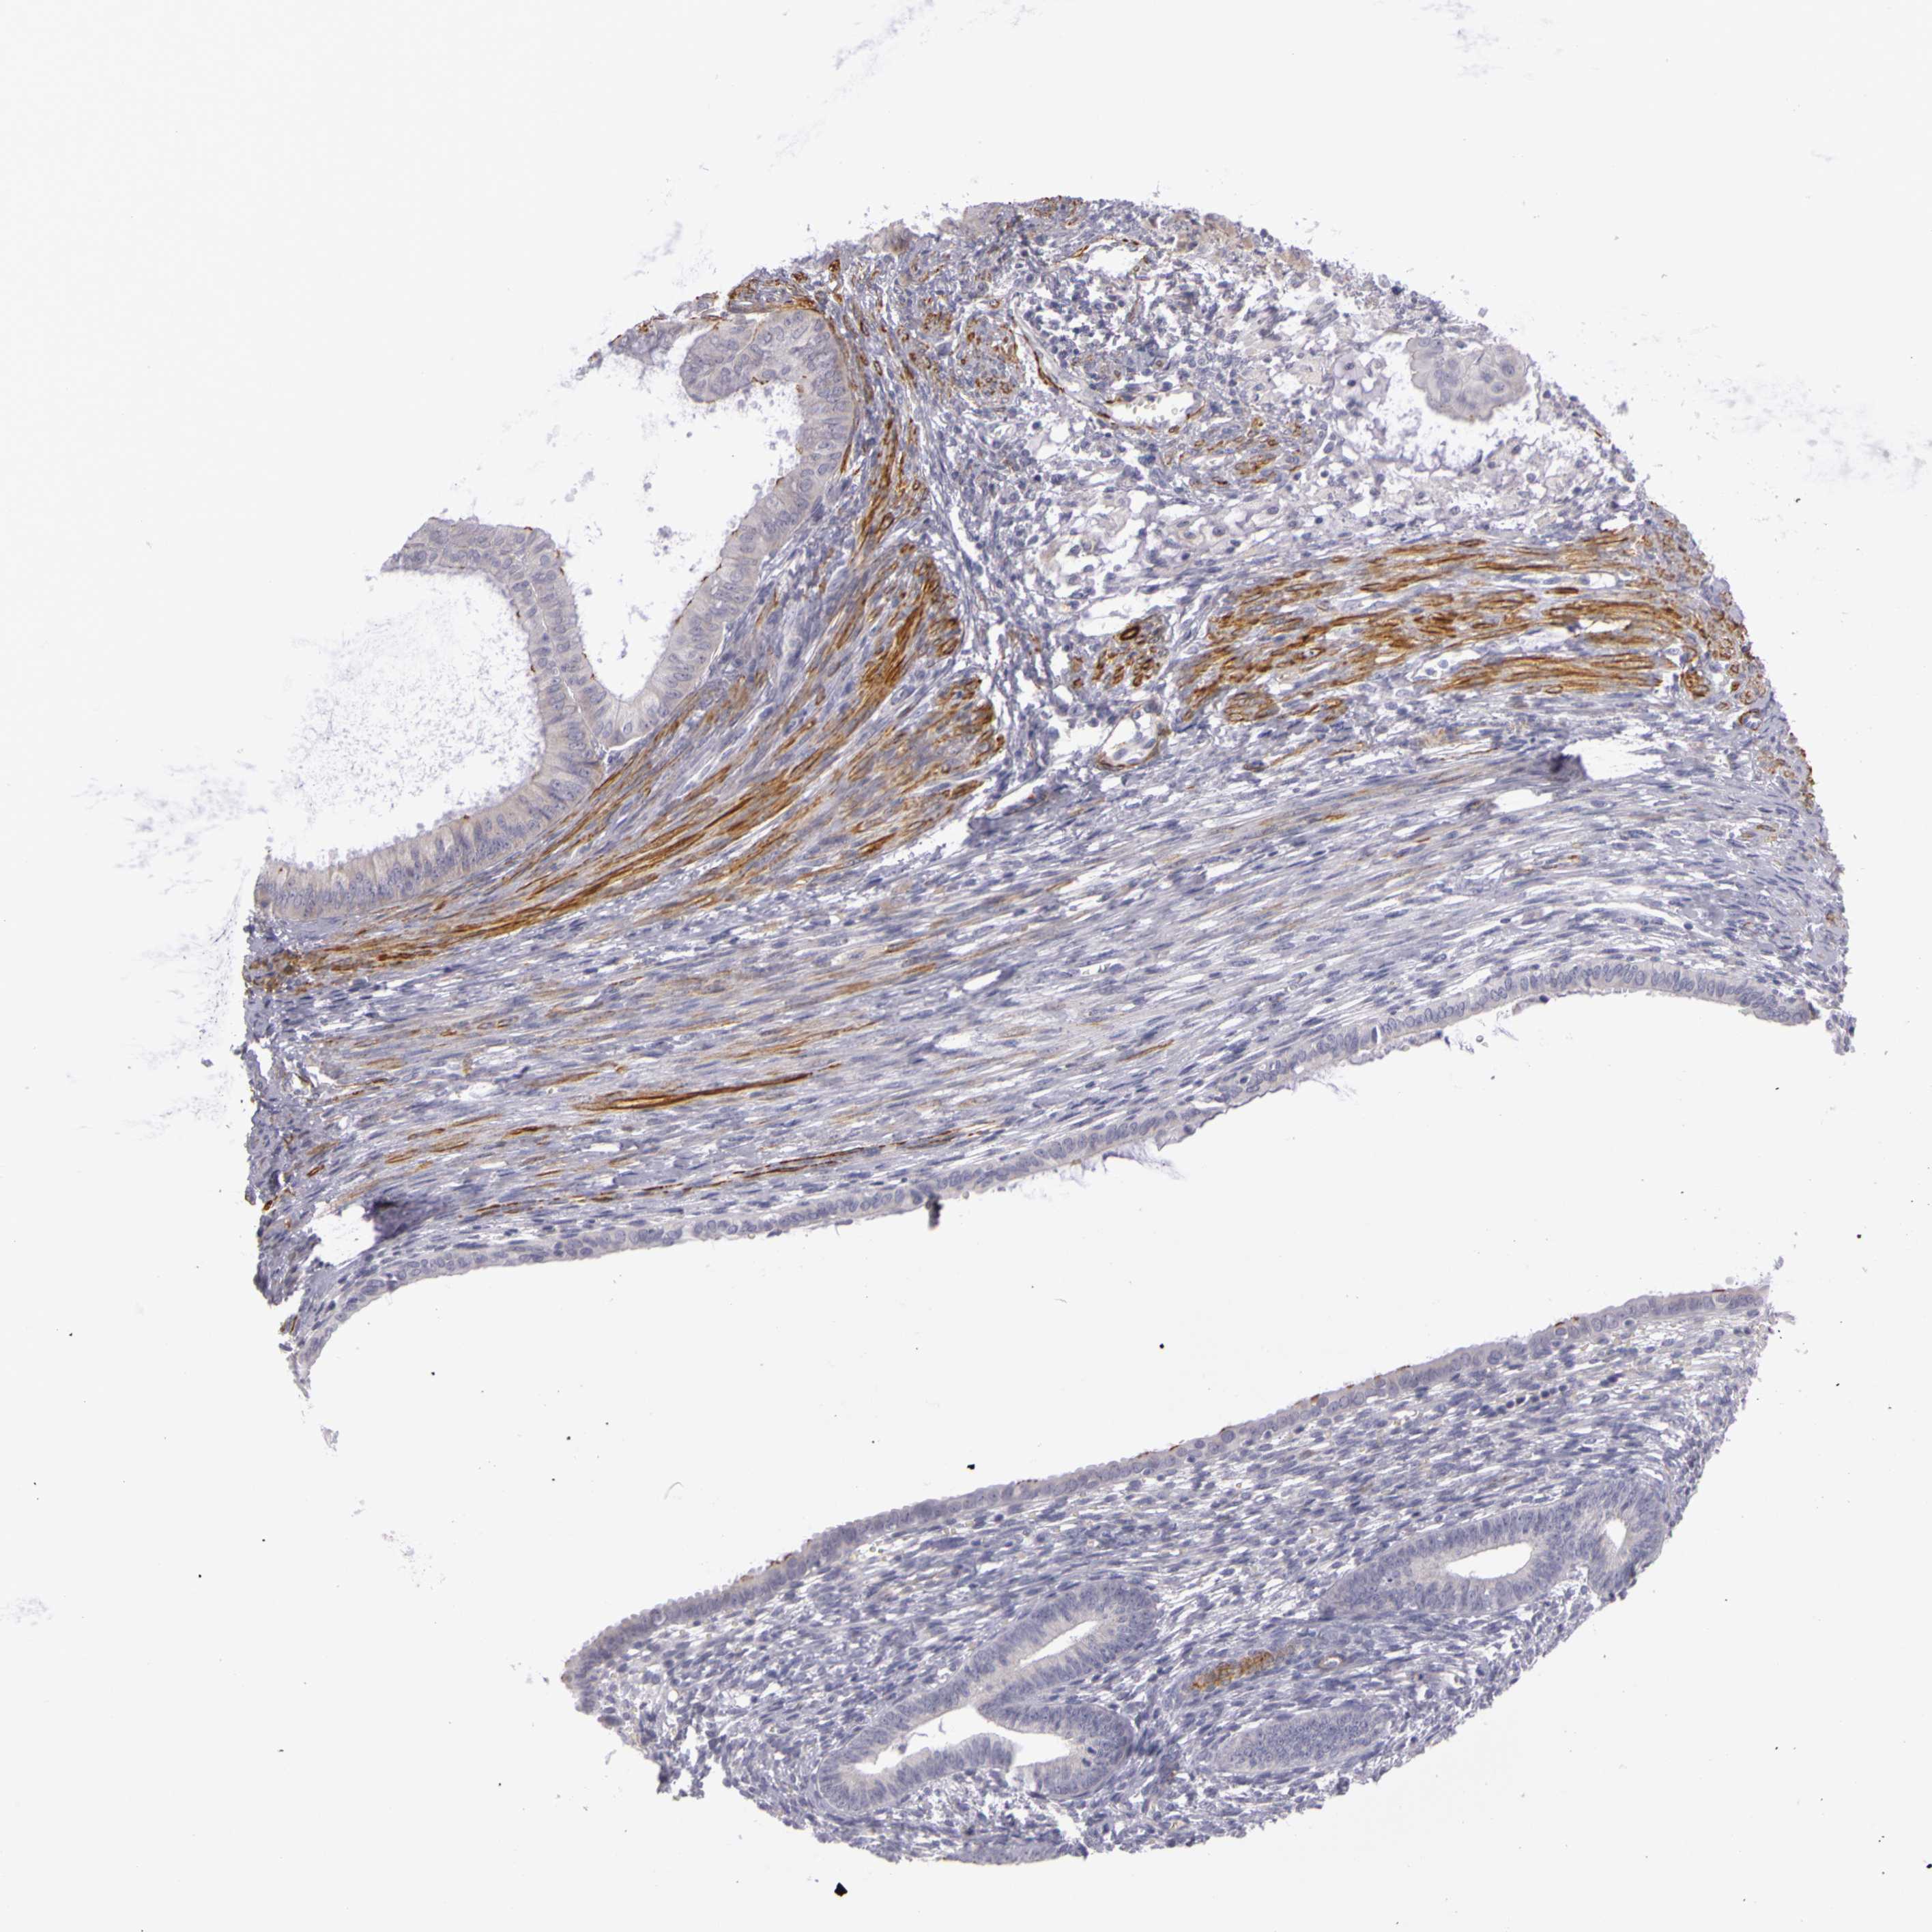

ENDOMETRIAL CANCER - Protein expressioni

A mouse-over function shows sample information and annotation data. Click on an image to view it in a full screen mode. Samples can be filtered based on level of antibody staining by selecting one or several of the following categories: high, medium, low and not detected. The assay and annotation is described here.

Note that samples used for immunohistochemistry by the Human Protein Atlas do not correspond to samples in the TCGA dataset.

Antibody stainingi

Antibody staining in the annotated cell types in the current human tissue is reported as not detected, low, medium, or high, based on conventional immunohistochemistry profiling in selected tissues. This score is based on the combination of the staining intensity and fraction of stained cells.

Each image is clickable and will lead to virtual microscopy that enables deeper exploration of all samples and also displays staining intensity scores, fraction scores and subcellular localization as well as patient and tissue information for each sample.

Antibody HPA001397

Antibody HPA012497

Staining

High

Medium

Low

Not detected

Intensity

Strong

Moderate

Weak

Negative

Quantity

>75%

75%-25%

<25%

None

Location

Nuclear

Cytoplasmic/membranous

Cytoplasmic/membranous,nuclear

Adenocarcinoma, NOS